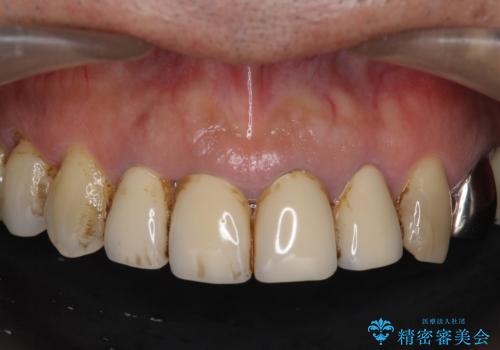

老朽化した前歯のクラウンやりかえ

- 10数年前に治療した上顎前歯のクラウンをやり替え、審美性を回復したいと希望され来院されました。

茶しぶの目立つ下顎前歯はPMTCを行うことで歯の自然な白さを回復しました。

- 48.4万円(税込)(仮歯・ジルコニアクラウン×4)費用は治療当時の料金となります